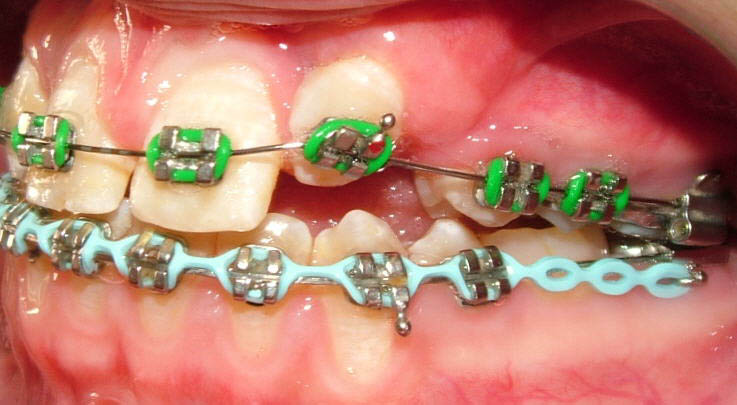

Faza a II-a a debutat cu un aparat fix ortodontic 2×2, aplicat la nivelul primilor molari şi al incisivilor centrali maxilari, în vederea derotării primului molar drept. Ulterior, s-au aplicat aparate fixe pe întreaga arcadă, cu scopul de a controla erupţia dentară. Caninul stâng superior a fost descoperit chirurgical într-o fază timpurie de tratament şi a durat aproximativ 18 luni pentru a putea fi aliniat pe arcadă (fig. 5). Pacienta a purtat elastice de clasa a doua pe partea stângă pentru a tracţiona caninul în poziţie; cu toate acestea, acest dinte nu a ajuns niciodată în raportul de clasa I, neutral, dorit.